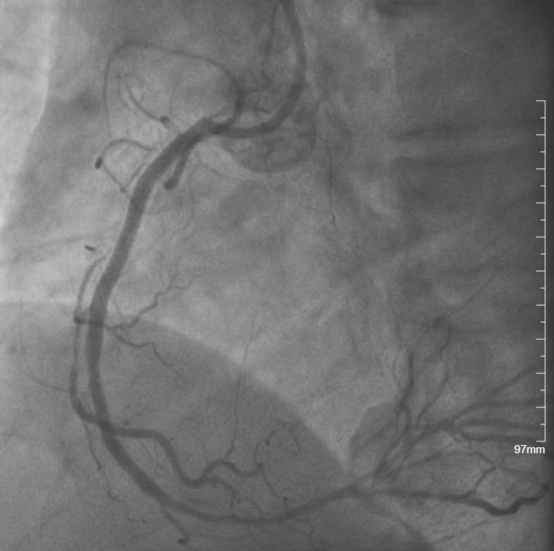

◆成功开通右冠状动脉急性闭塞病变